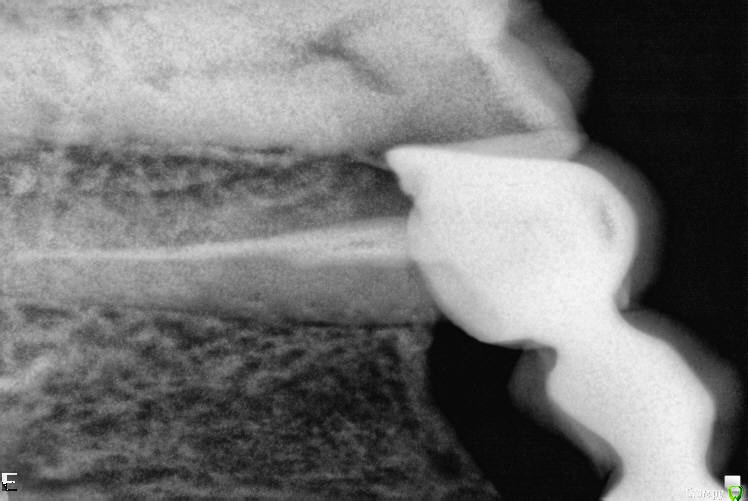

Krevetka Опубликовано 4 февраля, 2016 Поделиться Опубликовано 4 февраля, 2016 Коллеги, помогите пожалуйста с диагнозом. Или подскажите к какому специалисту направить...Есть пациент (не мой, просто вызвалась помочь ))) ) с жалобами на боль в нижней челюсти. Со слов пациента: сначала боль была в области уха, потом в нижней челюсти (под ухом), потом в области виска. боль имеет разлитый характер, пульсирующая, постоянная. Раньше болела только левая сторона, сейчас начинает болеть и правая. При жевании боль немного уменьшаеться. Утром болит меньше, вечером больше, во время физической нагрузки начинает пульсировать в ухе. пациент был на консультации в ЛОРа, челюстно-лицевого, стоматолога, ревматолога, невропатолога... точный диагноз так никто и не поставил. есть панорамный ртг (до лечения в стоматолога) Ссылка на комментарий

Елена Миллер Опубликовано 5 февраля, 2016 Поделиться Опубликовано 5 февраля, 2016 пульпит 47, обострение Ссылка на комментарий

ЕленаВалерьевна Опубликовано 5 февраля, 2016 Поделиться Опубликовано 5 февраля, 2016 а мне и 4.6 не нравится, ну и 4.7 наверняка пульпит, согласна с Еленой Миллер. и даже по описанию жалоб классические пульпитные боли. Ссылка на комментарий

annda Опубликовано 5 февраля, 2016 Поделиться Опубликовано 5 февраля, 2016 (изменено) Болит левая сторона от обострения пульпита в 47?Миофасциальная боль,триггерные точки надо искать в шее и жевательных мышцах.Справа пульпитный зуб есть.Болеть имеет право. Изменено 5 февраля, 2016 пользователем annda Ссылка на комментарий

Krevetka Опубликовано 5 февраля, 2016 Автор Поделиться Опубликовано 5 февраля, 2016 панорама была сделана до лечения у стоматолога. со слов пациента, ротовая полость сейчас полностью санорованакак Вам сказать.... полностью санирована.... Сегодня еще с ним списывались, выложеная панорама - это панорама "до", панорама "после" отличается тем, что на 38, 45, 46, 47 стоят пломбы. Эндо в 37 не делали, в 47 - пациент сам не знаетНачинает болеть правая сторона-сомневаюсь, что в 47 вылечен пульпит. В 38 тоже пульпит под вопросом.... 80% таких болей имеют стоматологическую этиологию. рекомендовала пациенту провести нормальную санацию полости рта. думаю, он в эти 80% попадает. если же нет-по рекомендации невропатолога- рентген сустава, возможно консультация нейрохирурга, возможно мрт головы. как-то так Ссылка на комментарий